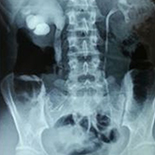

We evaluated a total of 32 children under the age of 18 years treated with ureteroscopic holmium laser lithotripsy for impacted ureteral stones between January 2005 and July 2013. Their stone-free state was defined as the absence of any residual stone on radiologic evaluation performed 4 weeks postoperatively. Complications were evaluated according to the modified Clavien classification.

The mean patient age was 9.5±5.1 years (range 1–18 years). Seven (21.8%) of the stones were located in the proximal ureter, 9 (28.2%) were in the mid-ureter, and 16 (50%) were in the distal ureter. The mean stone size was calculated as being 10.46±3.8 mm2 (range 5–20). The stone-free rate was 93.75% (30/32 patients) following primary URS. Additional treatment was required for only 2 (6.25%) of the patients. After the procedure, a D-J stent was placed in all the patients. The total complication rate was 15.6% (5 patients). The 10 total complications in these 5 patients were 5 (15.6%) Grade I, 1 (3.1%) Grade II, 2 (6.25%) Grade IIIa, and 2 (6.25%) Grade IIIb. The mean follow-up period was 16.5 months (range 3–55).